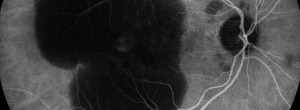

Intra and interobserver agreement in the classification of fundus autofluorescence patterns in geographic atrophy secondary to age-related macular degeneration.

Update on Geographic Atrophy in Age-Related Macular Degeneration.